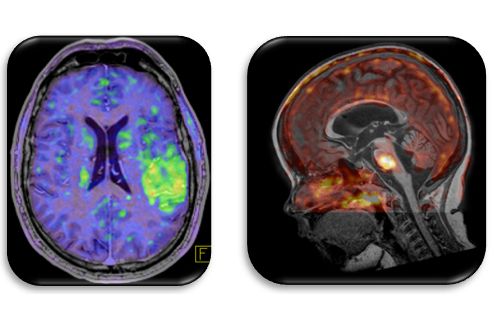

Innovative Training Network ITN ist ein spezielles Förderprogramm, das Netzwerke fördert, die NachwuchsforscherInnen ausbilden. Das Training Network „HYBRID“ (Healthcare Yearns for Bright Researchers for Imaging Data, MSCA-ITN-ETN 764458), fokussiert sich auf die hybride, molekulare Bildgebung mit Schwerpunkt PET/MR. Konkret besteht das Programm aus 3 Arbeitspaketen, welche die multi-zentrische Datenerhebung, eine multi-parametrische Auswertung und die Translation neuer Diagnostikansätze in die Klinik beinhalten. Dabei werden in den kommenden vier Jahren standardisierte quantitative Auswerteverfahren für die multi-parametrische Bildgebung entwickelt, welche – zusammen mit weiteren Biomarker Informationen (z.B. Histologie, Liquid Biopsy) – über eine rein visuelle Beurteilung von Bilddaten hinausgeht. Der multi-zentrische Ansatz und die bevorzugte Verwendung von integrierten, hybriden Bildgebungsmethoden sind eine Besonderheit dieses Vorhabens. Schlussendlich sollen die Erkenntnisse aus den verschiedenen Forschungsbereichen zu verbesserten Diagnosemethoden (inkl. prädiktive Modelle; Stichwort „RadiomicsPlus“) und neuen Ansätzen für bildgestützte Therapien führen.

Abbildung: Personalized medicine through HYBRID: Patients with suspected disease undergo standardized examination protocols for the collection of biomarker information (image and non-image based information). Data are processed and interpreted prior to making a diagnosis. Decision models are supported by machine learning algorithms. In addition, diagnostic and complementary information is pooled and used for a population-based analysis and subsequent pre-selection of clinical patients for individual imaging and/or therapy options. HYBRID’s entangled research-based work packages, WP1-3, cover novel aspects of data collection, data processing and clinical translation.